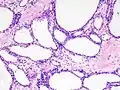

Micrograph showing a pancreatic serous cystadenoma. H&E stain. | |